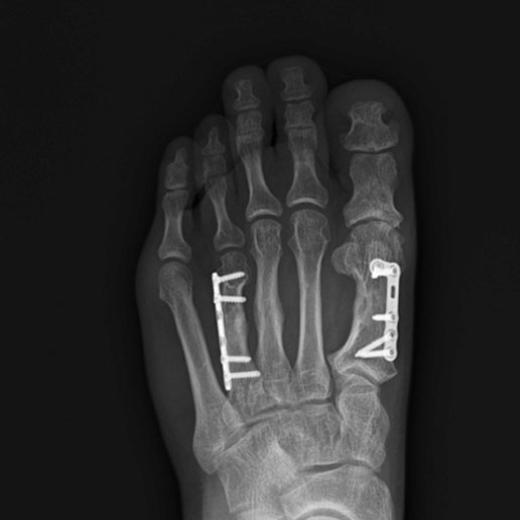

단지증 수술 전/후 예시

단지증 수술 후

2020.12.03

ㆍ환자 동의를 받은 자료이며, 이미지 사진은 실물과 다를 수 있습니다.

ㆍ모든 자료는 새움병원 자료입니다.